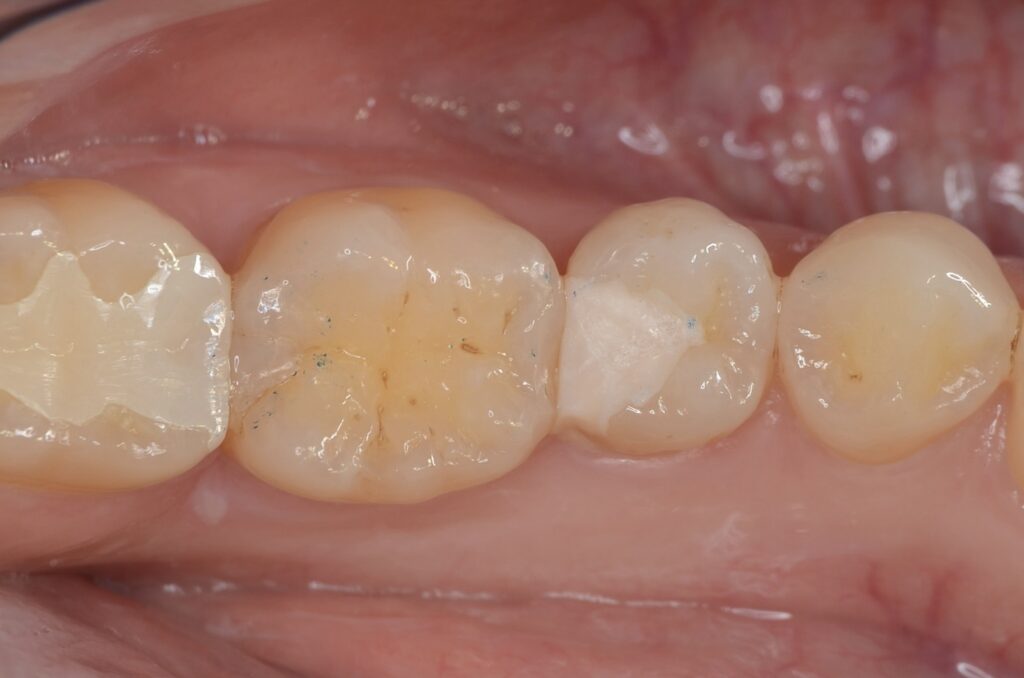

40代 虫歯治療 ダイレクトボンディング #52

Before

After

| 年齢 | 40代 | 治療方法 | ダイレクトボンディング |

|---|---|---|---|

| 性別 | 男性 | 通院回数 | 2回 |

| 主訴 | むし歯を治したい | 費用 | 115,500円(税込) |

| 治療のメリット | 歯を削る量を少なくできる・自然な見た目・境目がピッタリできる | ||

| 治療のデメリット | 大きい虫歯治療には適応できない場合がある | ||